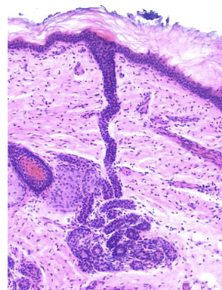

Skin glands - 4 types

Sebaceous (oil) gland

eccrine sweat glands

Apocrine sweat gland

cerumious glands

Sebaceous (oil) glands

connected to hair follicles

Eccrine v. Apocrine sweat glands

Eccrine - the most numerous, all over body

Apocrine - located mainly in hairy skin areas, stinky sweat